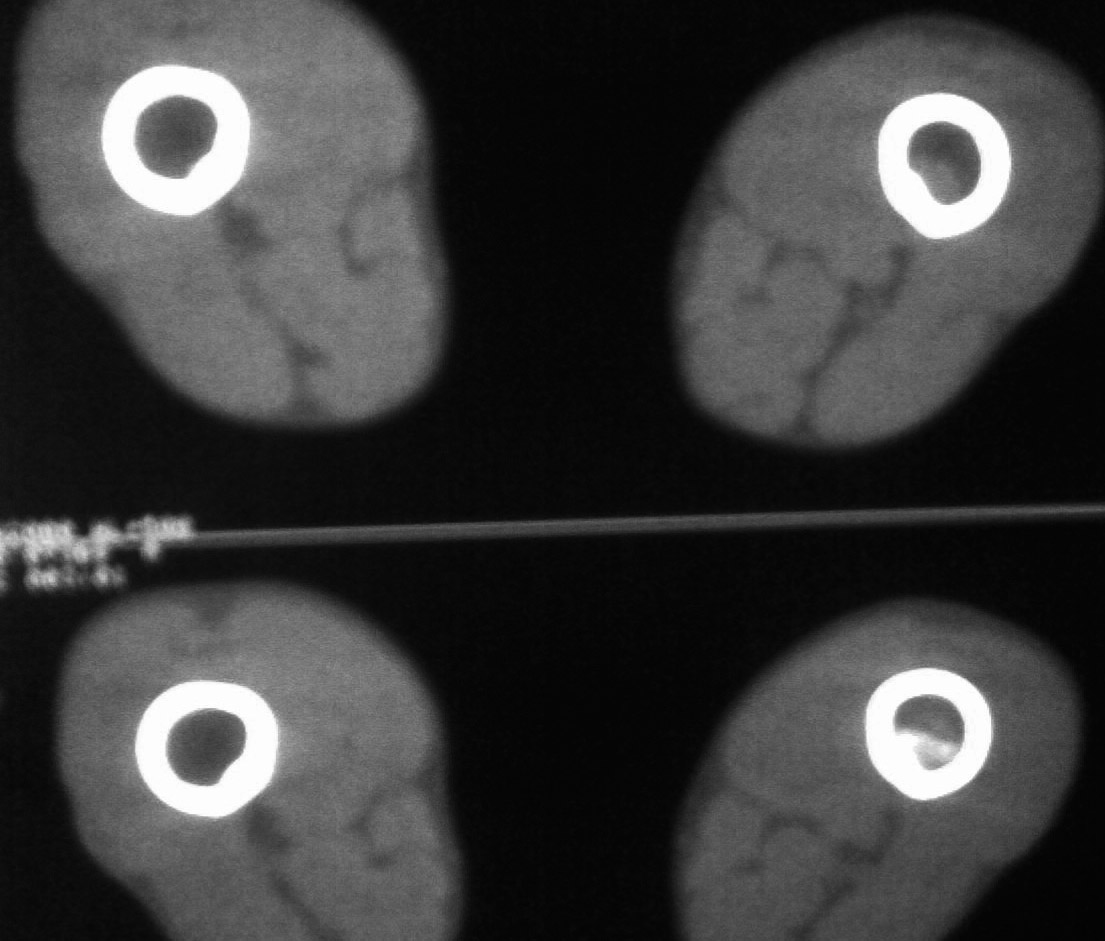

资料不是太清晰,考虑恶性骨肿瘤可能性大

恶性肿瘤可能性大,伴病理性骨折